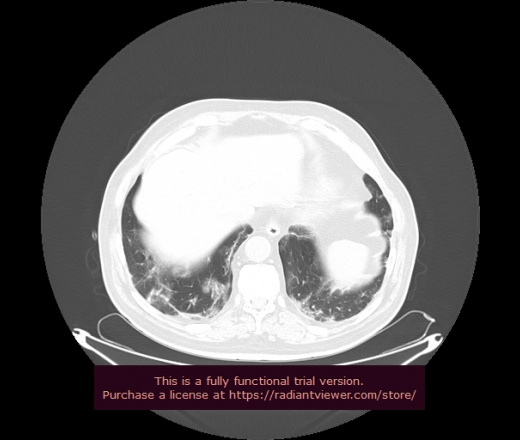

Уважаемые коллеги, если имеется интерес, сможете ли Вы спрогнозировать дальнейшее +-одинаковое течение процесса у 4 данных разных пациентов? Зацепиться где-то можно очень просто, где-то нельзя.